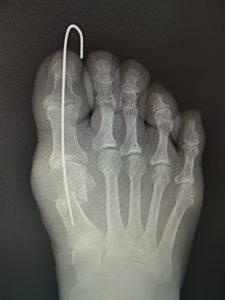

手術前 手術後4年

最近では、原則として固定ワイヤーは経皮的の一本のみとし、ワイヤーの先端は皮膚の外に出ているので、抜く時(術後3週間目)の患者さんの負担はほぼありません。こうすることによるデメリットはなく、むしろ術後成績は良くなっています。

(図6)

手術前 手術後

真田理事長による手術の様子。外反母趾|症例 (左から 手術前、手術後、ワイヤ抜去後)